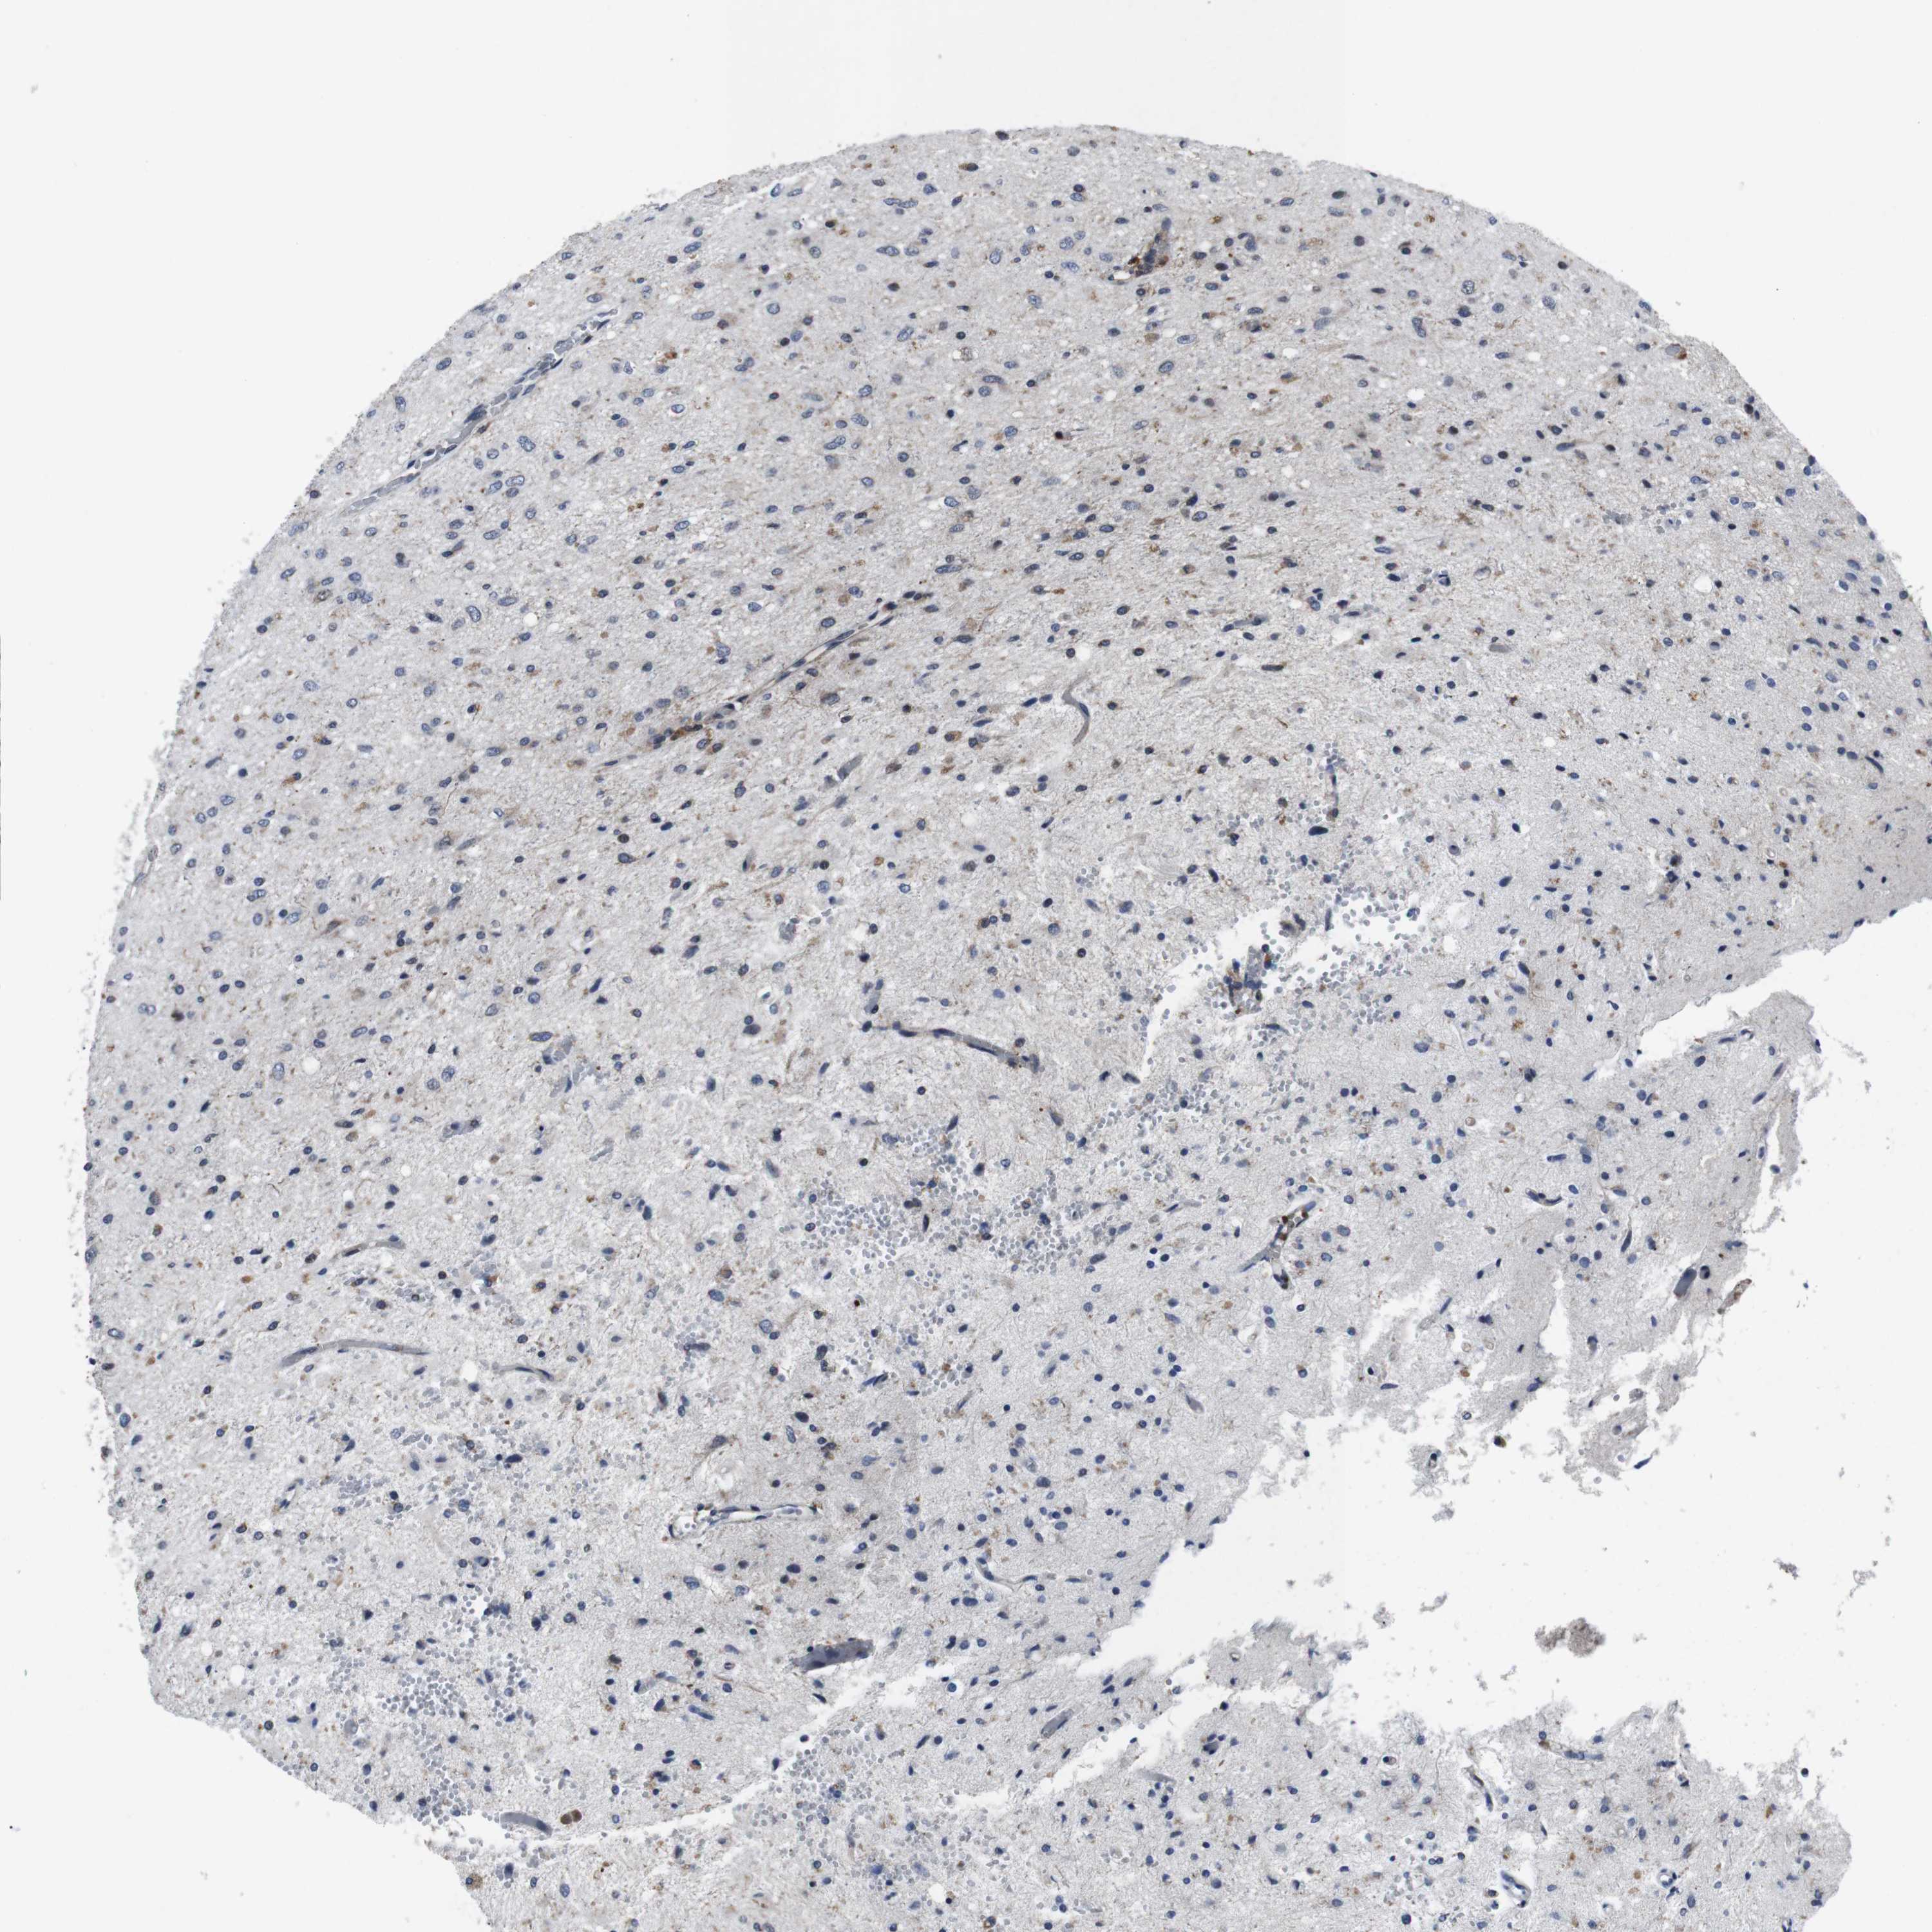

GLIOMA - Protein expressioni

A mouse-over function shows sample information and annotation data. Click on an image to view it in a full screen mode. Samples can be filtered based on level of antibody staining by selecting one or several of the following categories: high, medium, low and not detected. The assay and annotation is described here.

Note that samples used for immunohistochemistry by the Human Protein Atlas do not correspond to samples in the TCGA dataset.

Antibody stainingi

Antibody staining in the annotated cell types in the current human tissue is reported as not detected, low, medium, or high, based on conventional immunohistochemistry profiling in selected tissues. This score is based on the combination of the staining intensity and fraction of stained cells.

Each image is clickable and will lead to virtual microscopy that enables deeper exploration of all samples and also displays staining intensity scores, fraction scores and subcellular localization as well as patient and tissue information for each sample.

Antibody HPA001860

Antibody CAB013108

Staining

High

Medium

Low

Not detected

Intensity

Strong

Moderate

Weak

Negative

Quantity

>75%

75%-25%

<25%

None

Location

Nuclear

Cytoplasmic/membranous

Cytoplasmic/membranous,nuclear

Glioma, malignant, High grade

Glioma, malignant, Low grade